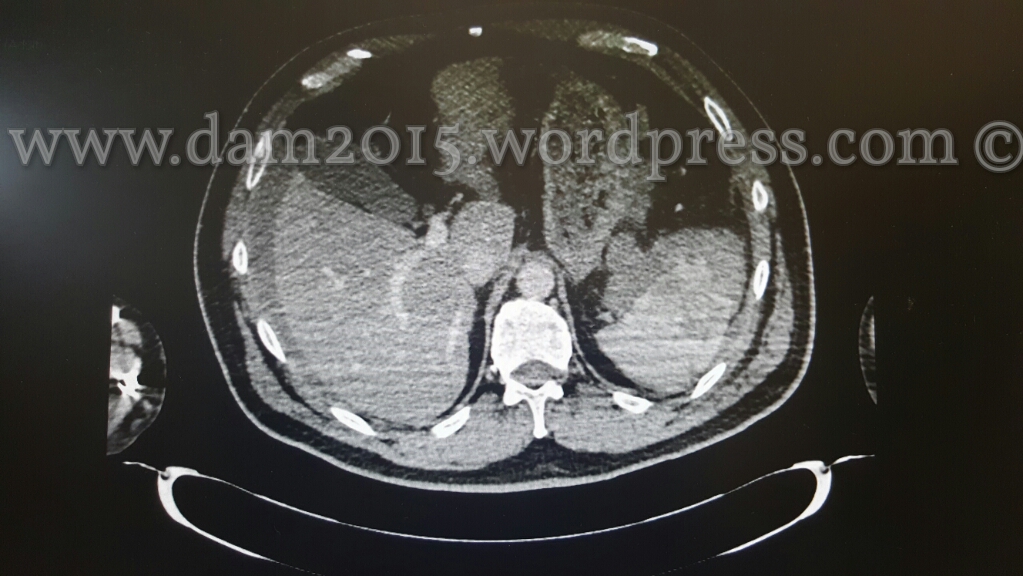

Pz uomo, 56anni.

Incidente stradale moto-auto.

Rottura di milza in due tempi. Emoperitoneo.

Splenectomia.